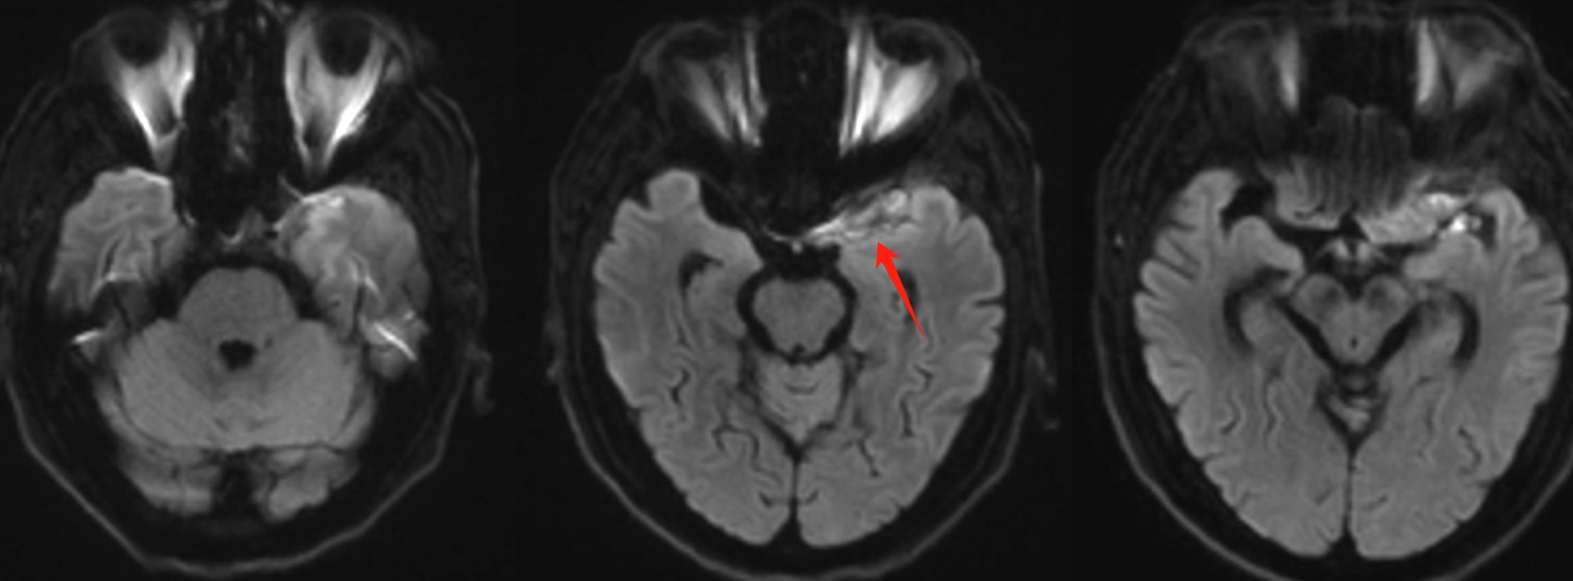

该患者入院后完善常规颅脑影像学检查,左侧颞叶病变,疾病性质不详,转移瘤、胶质瘤、炎症类疾病均不能排除,遂行PET-CT检查,提示左侧颞叶高代谢,淋巴瘤不能排除。组织MDT会诊建议可先行腰椎穿刺查脑脊液脱落细胞学、感染指标,若仍不能确诊,可进一步行开颅病灶切除,术中快速冰冻,根据冰冻结果决定手术手术策略。患者脑脊液脱落细胞学结果:较多淋巴细胞,少许单核细胞及个别中性粒细胞,未见异形细胞,脑脊液常规、生化、脑脊液培养未见细菌生长,诊断仍不能明确,且患者病情进展迅速,患者神志呈昏睡状态,颅脑MRI提示病变较前明显增大(影像学检查间隔两周),且水肿明显加重,遂行开颅病变切除术。术中见部分病变累及蝶骨嵴硬膜,病变质地硬韧,内有多个囊腔,囊内容物为黄色粘稠样脓性物质,留取囊液及实性部分送快速冰冻,在等待冰冻过程中,进一步探查见肿瘤侵犯左侧颞叶,该部位肿瘤质地相对软,无包膜,与周围脑组织无边界,血运不丰富,内有多个囊腔,且肿瘤侵犯侧裂池、颈动脉池,左侧视神经、颈内动脉、大脑中动脉均被病变包绕,且该处肿瘤质地偏硬韧。术中快速冰冻提示组织大片变性坏死,伴胶质增生及淋巴增生。结合病变质地及冰冻结果,考虑为非肿瘤性疾病,可能为炎性病变伴肉芽肿形成可能性大,且肿瘤质地硬韧,累及范围广泛,难以全切,遂行肿瘤大部分切除后结束手术。术后病理结果明确后予以伏立康唑、醋酸卡泊芬净抗真菌治疗。在治疗过程中患者先后出现脑出血、脑梗塞,最终因治疗周期长,花费高、效果不确定等因素,家属放弃治疗,于术后1月去世。

颅内曲霉菌病(intracranial aspergillosis,ICA),又称中枢神经系统曲霉菌病,是一种由曲霉菌侵袭感染脑实质、脑膜(硬脑膜为主)、脑血管及海绵窦等颅底结构引起的侵袭性真菌病。ICA由Oppe首次报道于1897年,该病临床少见,但随着激素、免疫抑制剂及广谱抗生素的广泛应用,其发病率逐年上升。ICA的临床及影像学表现缺乏特异性,核心症状异质性大,诊断及鉴别诊断困难。ICA占颅内真菌感染的5%-10%,占侵袭性曲霉菌感染的14%-42%,ICA更易累及男性,男女比例为2.25∶1。曲霉菌在自然界中广泛存在,是一种机会致病菌。其分生孢子可经呼吸道进入人体,定植于肺部、鼻窦等空腔内。当机体免疫力降低时,曲霉菌在组织、器官或血液中生长、繁殖,导致炎性反应及组织损伤,可经两种途径即局部浸润及血行播散侵入颅内导致ICA。据报道,18.0%-66.7%的患者由鼻窦、中耳及乳突中的曲霉菌感染浸润引起(窦源性ICA),该患者合并慢性鼻窦炎,考虑为窦源性。ICA可累及脑血管、脑实质、脑膜(硬脑膜为主)及颅底结构,导致坏死、化脓及慢性肉芽肿。曲霉菌侵及脑血管后,既可因菌丝填充或炎性反应导致脑梗死,又可因曲霉菌性动脉瘤破裂导致脑出血或蛛网膜下腔出血。该病多呈急性或亚急性起病,进行性加重,临床表现多样且缺乏特异性。

GM实验,GM是曲霉菌细胞壁的主要成分,是疾病早期释放至体液中的抗原之一。据报道,脑脊液GM试验诊断ICA的敏感度及特异度分别为88.2%及96.3%,且阳性预测值及阴性预测值均超过90%,脑脊液GM水平与曲霉菌感染严重程度相关,监测该指标可评价治疗效果及预后。影像学检查具有多样性,多为反复慢性炎症、肉芽肿样改变,部分易累及颅底。

目前确诊ICA仍依赖于病灶切除或活检,获得组织病理学、直接镜检或培养证据。《颅内曲霉菌病诊治中国专家共识》推荐:当临床症状怀疑ICA时,应尽早行脑脊液检查(常规、生化、培养、G试验、GM试验及mNGS)及颅脑MRI平扫+增强检查。怀疑窦源性ICA时,还应加做颅底CT检查。当临床症状符合ICA,但上述检查结果为阴性时,可重复送检。条件允许时,及时行标本镜检与培养获得确切证据。尤其是对于长期应用激素、免疫功能缺陷高危患者。